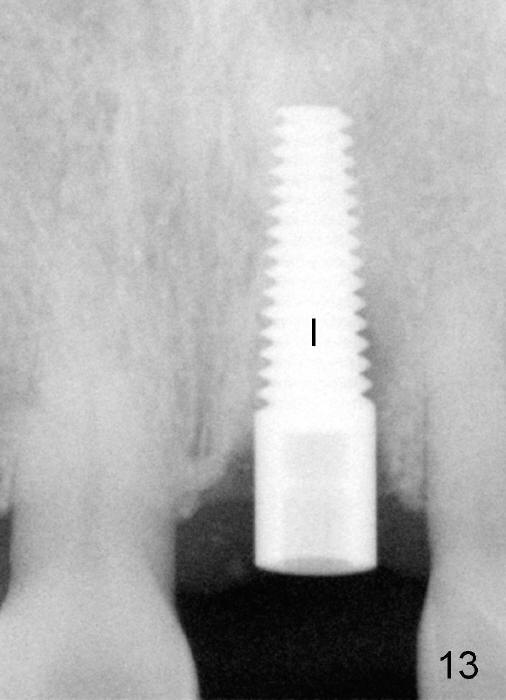

A 60-year-old lady had an abscess mesial to #9 six years ago (Fig.1,2 <), treated as a perio lesion by laser (Fig.3) and osseous surgery without bone graft (Fig.6, followed by CT exam revealing semi-circumferential bone loss (Fig.4,5). When the perio treatment failed, attention was paid to endo aspect (Fig.7-9). In fact the pulp was found to be vital when access to root canal therapy was made. As expected, the treatment failed again. The palatal fistula persisted. The infection was suspected to be a source of remote immediate implant site (#30). The tooth #9 was extracted. It appears that there is a semilunar crack line in the linguomesial root (Fig.12). When the socket healed 2 weeks post extraction (Fig.10), the #30 buccal defect was debrided with bone graft. There was no bone resorption 4 weeks post extraction (Fig.11); a 4.5x17 mm implant was placed (Fig.13-15). An immediate provisional was fabricated (Fig.16-18). Fig.19,20 were taken 3 months post implantation and 7 months post cementation, respectively. Dense bone forms around the implant coronally 4 years 5 months post cementation (Fig.21), while the gingiva is healthy palatally (Fig.22) and buccally (Fig.23).